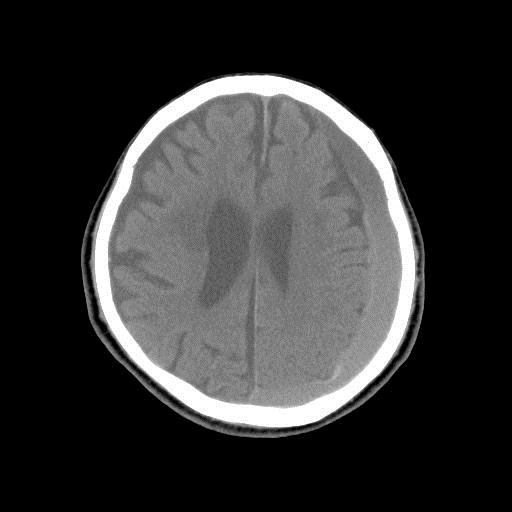

On Day 5, CT of the head was performed and near complete evacuation of the hematoma was observed (Figure 1B). However, on Day 6, the patient had an altered level of consciousness following the sudden efflux of a large amount of subdural effusion from the drainage system. CT of the head revealed an acute subdural hematoma on the contralateral side, with a midline shift to the left and compression of the ipsilateral lateral ventricle (Figure 1C). Under general anesthesia, a craniotomy was made over the right frontotemporoparietal region, and the subdural hematoma was observed in the space between the dura and an inner membrane (Figure 2A). Following the removal of the hematoma, bleeding from the torn bridge vein was observed, and the bleeding vein was coagulated (Figure 2B). An intracranial pressure monitoring system provided measurements of intracranial pressure at a subdural level, and consistently low intracranial pressure (-3-5mmHg) was recorded. The second postoperative course was uneventful. The patient was discharged 20 days later with mild neurological deficit.

| Figure 1C: Postoperative CT revealing a contralateral acute hematoma, suggesting a subdural hematoma with a midline shift to the left and compression of the ipsilateral lateral ventricle |